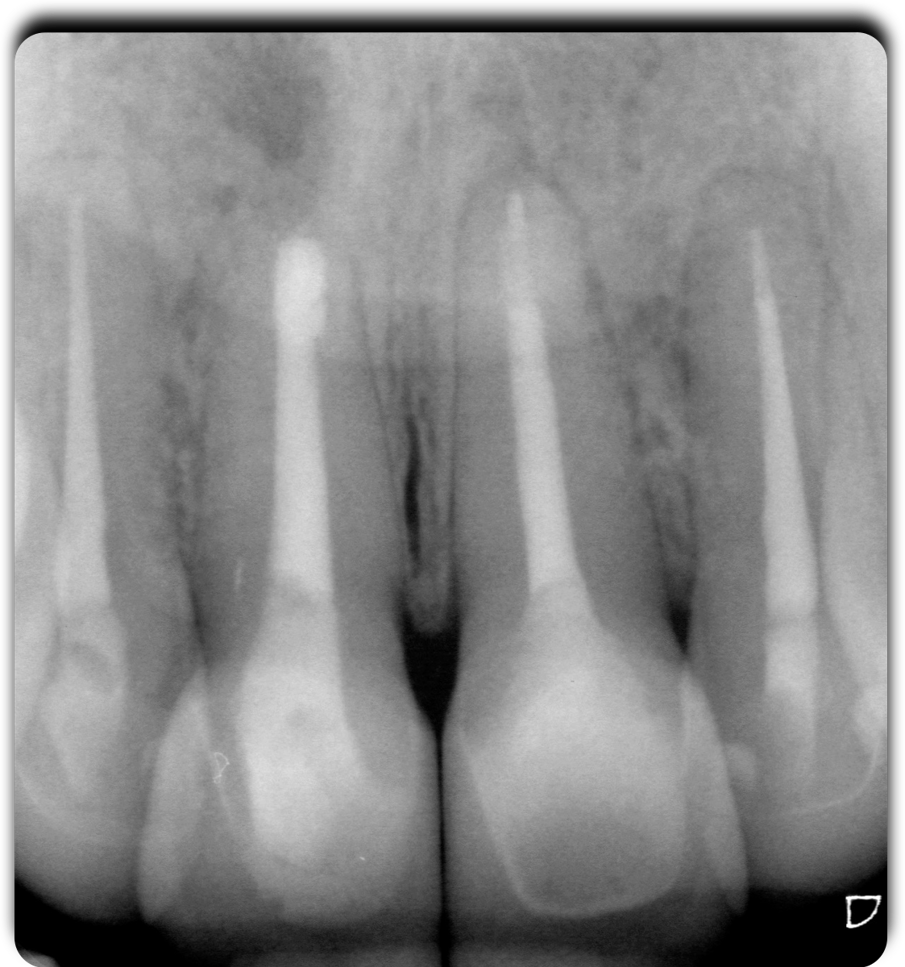

Fig. 3 - Lo stato endodontico iniziale.